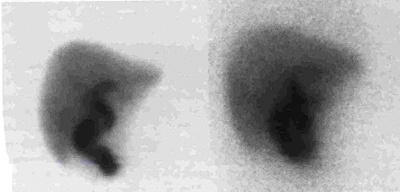

בדיקת עזר אחרת היא מיפוי דרכי המרה על-ידי Hida או Dipa. חומרים מסומנים אלה מופרשים דרך הכבד לדרכי המרה ולמערכת העיכול. בדרך כלל בתוך 15 דקות מההזרקה אפשר להדגים חומר בכבד, בכיס המרה ובמערכת העיכול. בצהבת חסימתית לא תיראה הפרשה למעי, או שתתגלה הפרשה קלושה לאחר יותר מ- 4 שעות מתחילת הבדיקה (תצלום 31.8).